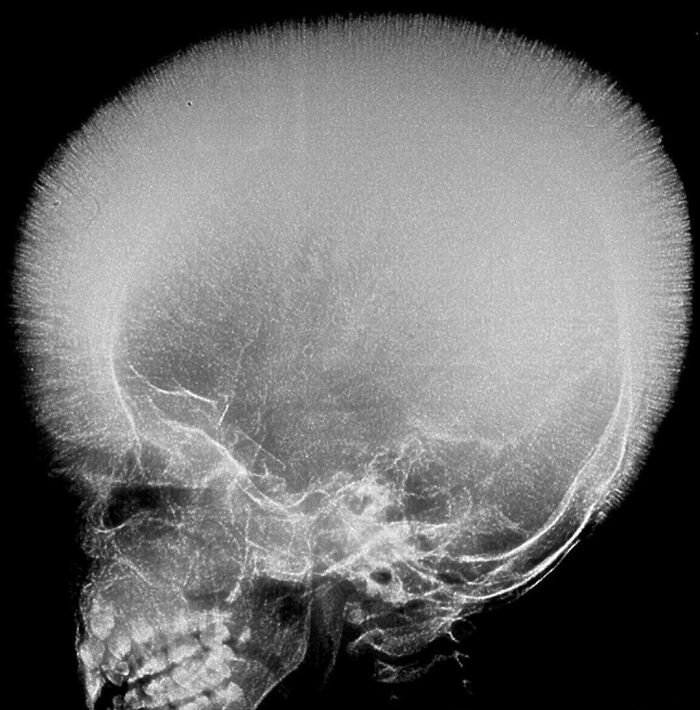

Una mujer de 52 años presentó una hinchazón del cuero cabelludo indolora y de agrandamiento gradual.

Perdón si es algo grave, pero parece la radiografía de un micrófono